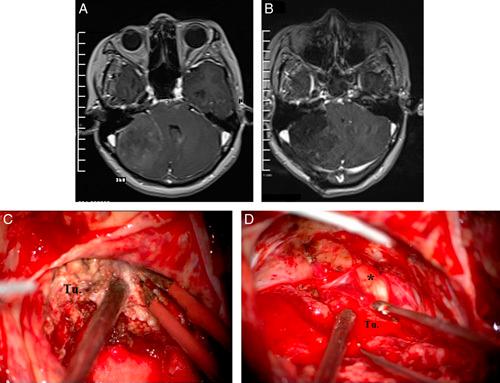

Cerebellopontine angle (CPA) meningiomas are the second most common tumor of the CPA. Depending on the site of dural attachment, the relationship between the tumor and critical neurovascular structures of the CPA is variable. This study aims to evaluate the influence of CPA meningioma location in relation to the internal auditory canal (IAC) on clinical symptoms, radiological presentations, and surgical treatments and outcomes which has been rarely reported in Vietnam.

A prospective study on 33 patients treated with microsurgery from August 2020 to May 2022 at the Neurosurgery Center, Viet Duc University Hospital.

The mean age of 27 females (85%) and 6 (15%) males was 54±12 years. Based on their location to the IAC, there were 16 premeatal cases (49%) (anterior to the IAC) and 17 retromeatal cases (15%) (posterior to the IAC). The time of diagnosis of the retromeatal group was later (16.5 vs. 9.7 months), the average tumor size of the 2 groups was not different, but when there was brainstem compression, the average tumor size of retromeatal group was larger (49 vs. 44 mm). The clinical presentations of the retromeatal group were related to the cerebellar symptoms, while trigeminal neuropathy symptoms all came from the premeatal group. Gross total resection of the premeatal group was 31% and of the retrometal group was 71%. The results of preserving the facial nerve function of the premeatal group were lower (44 vs. 82%). Postoperative Karnofsky score of the retromeatal group improved, while the premeatal group did not change.

Classification of CPA meningiomas according to their location to the IAC plays an important role in diagnosis and treatment, affecting clinical symptoms, surgical strategy as well as surgical outcomes.

桥小脑角(CPA)脑膜瘤是CPA区第二常见的肿瘤。根据硬脑膜附着部位,肿瘤与CPA区关键神经血管结构的关系各不相同。本研究旨在评估CPA脑膜瘤相对于内耳道(IAC)的位置对临床症状、影像学表现、手术治疗及预后的影响,而这在越南鲜有报道。

对2020年8月至2022年5月在越德大学医院神经外科中心接受显微手术治疗的33例患者进行前瞻性研究。

27例女性(85%)和6例男性(15%)的平均年龄为54±12岁。根据其相对于IAC的位置,有16例耳前病例(49%)(IAC前方)和17例耳后病例(51%)(IAC后方)。耳后组的诊断时间较晚(16.5个月对9.7个月),两组的平均肿瘤大小无差异,但当出现脑干受压时,耳后组的平均肿瘤大小更大(49 mm对44 mm)。耳后组的临床表现与小脑症状相关,而三叉神经病变症状均来自耳前组。耳前组的全切率为31%,耳后组为71%。耳前组保留面神经功能的结果较低(44%对82%)。耳后组术后卡诺夫斯基评分提高,而耳前组无变化。

根据CPA脑膜瘤相对于IAC的位置进行分类在诊断和治疗中起着重要作用,影响临床症状、手术策略以及手术预后。